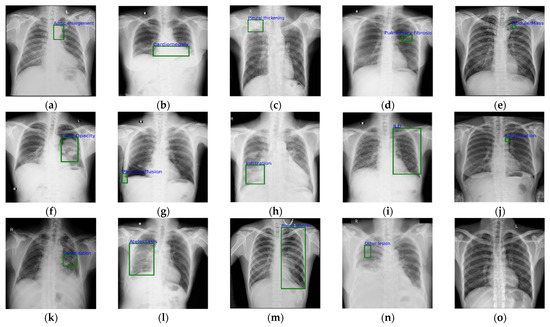

In this study, we used the VinDr-CXR chest X-ray dataset [41] collected from two hospitals in Vietnam for the experimental evaluation. A total of 15,000 images as the original data were provided to the academic community for scientific research, including 10,606 normal chest images and 4394 abnormal chest target images. The chest X-ray abnormalities in the VinDr-CXR dataset were further divided into 14 abnormal types. The number of each type is shown in Table 1, and sample images of the various types are shown in Figure 4. It is worth noting that the public dataset we used was published and peer-reviewed, where the X-ray images were processed and there was no privacy or harm involved. During our research, we also strictly followed the ethics of using medical datasets.

Figure 4.

Samples with different abnormalities in the VinDr-CXR dataset: (a) aortic enlargement; (b) cardiomegaly; (c) pleural thickening; (d) pulmonary fibrosis; (e) nodule/mass; (f) lung opacity; (g) pleural effusion; (h) infiltration; (i) interstitial lung disease; (j) calcification; (k) consolidation; (l) atelectasis; (m) pneumo-thorax; (n) other lesion; (o) normal.